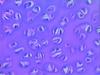

what is pictured

autonomic ganglia